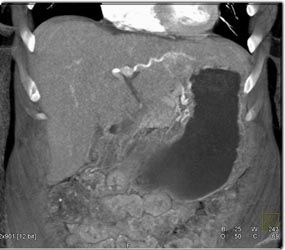

Cholangiocarcinoma Best Seen on Late Phase Images